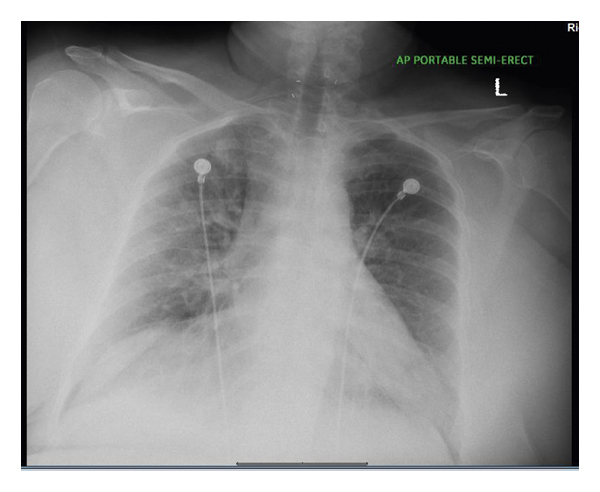

She decided to take a COVID-19 test which came back positive which prompted her to come to the ED. Her home medications included hydrocortisone 20 mg in the morning, 10 mg in the afternoon, and 5 mg at night, levothyroxine 112 mcg two tablets in the morning, and fludrocortisone 0.1 mg tab daily. Her vital signs were as follows: temperature, 98.7°F; blood pressure, 100/48 mmHg; heart rate, 98/min; and O2 saturation, 95% on 2 litres of nasal cannula and 88% on room air. Random blood glucose level is 136 mg/dl. Chest X-ray (Figure 1) showed bilateral infiltrates. Remdesivir 200 mg one time and 100 mg for 4 more days was started intravenously (IV) for acute hypoxic respiratory failure. Hydrocortisone 100 mg IV every 8 hours for 2 doses was given while awaiting the endocrinologist to see the patient, and the patient’s home medication fludrocortisone was held.